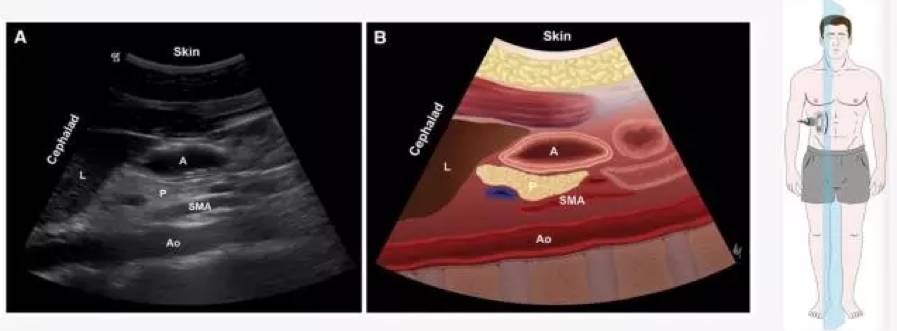

?影像定位:肝左叶、肠系膜上动脉和腹主动脉作为解剖标志

检查平面【1】